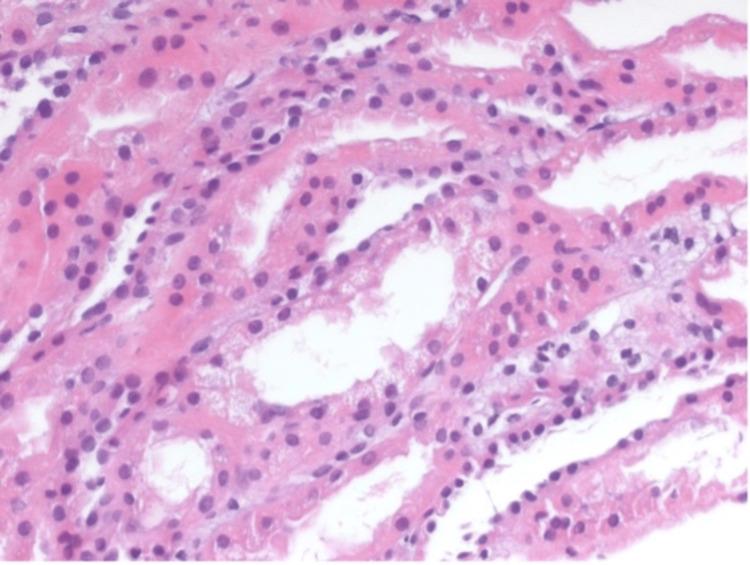

Acute tubular necrosis (ATN) is a serious medical condition characterized by the rapid destruction of renal tubular epithelial cells, resulting in acute kidney injury, given its multifactorial etiologies, which can include nephrotoxic agents, ischemic insults, hypovolemia, and sepsis. We report the case of a young male patient who presented with recurrent worsening kidney function with bland sediment that was confirmed with multiple kidney biopsies as recurrent attacks of ATN of unclear etiology, which did not respond to supportive measures but did respond to steroids.

急性肾小管坏死(ATN)是一种严重的医学病症,其特征是肾小管上皮细胞迅速破坏,导致急性肾损伤。鉴于其多因素病因,包括肾毒性药物、缺血性损伤、血容量不足和败血症等。我们报告了一例年轻男性患者的病例,该患者反复出现肾功能恶化,尿沉渣正常,经多次肾活检证实为病因不明的复发性ATN发作,对支持性措施无反应,但对类固醇有反应。